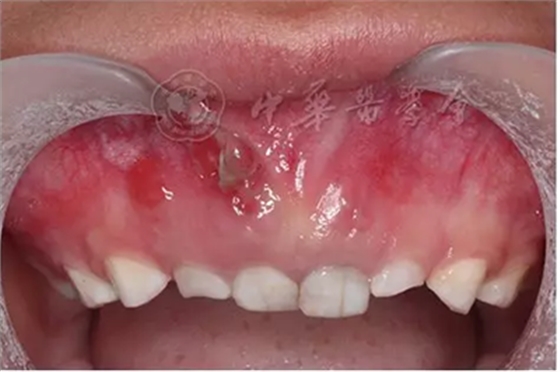

(1)疾病定義及口腔表現(xiàn):家族性低磷酸血癥佝僂病是一種以低磷血癥導(dǎo)致骨發(fā)育不良為特征的遺傳性骨病,是由于腎小管缺陷,重吸收磷減少,活性維生素D生成不足,以致鈣、磷代謝紊亂造成佝僂病,其遺傳方式為X連鎖顯性遺傳,致病基因?yàn)镻HEX基因。主要臨床特征為身材矮小、雙下肢彎曲、走路無(wú)力、腿痛、骨質(zhì)疏松和多發(fā)性骨折??谇槐憩F(xiàn)為乳牙和恒牙萌出遲緩,乳牙多發(fā)性自發(fā)性牙槽膿腫、牙齦瘺管,無(wú)齲和牙外傷病史(圖5),膿腫發(fā)生的順序與牙齒萌出順序一致。影像學(xué)檢查顯示牙槽骨密度減低,硬骨板消失。髓腔非常大,牙體硬組織薄。組織病理學(xué)檢查可見釉質(zhì)正常,但有時(shí)可見明顯裂隙,牙本質(zhì)小管間可見大的裂隙、陷窩。

圖5 5歲家族性低磷酸血癥佝僂病患兒右上乳中切牙唇側(cè)牙齦瘺管